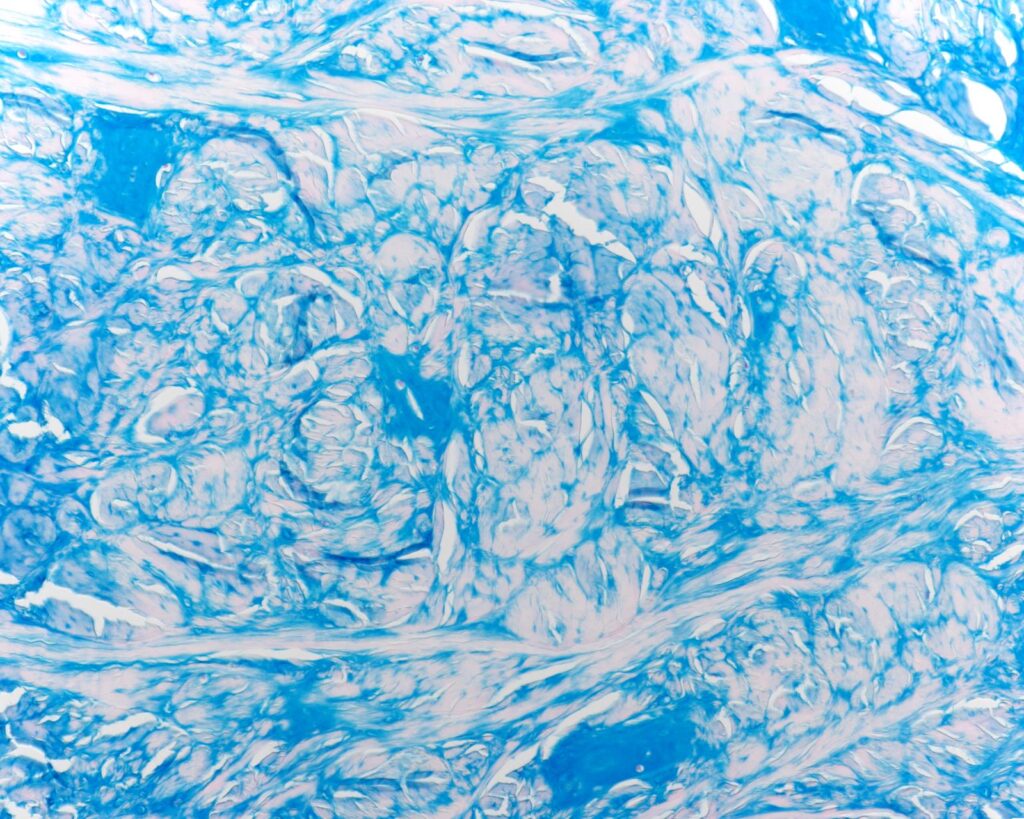

Preclinical Research

Pharmaceutical, biotechnology and medical device companies look to Biograding Solutions Pharmaceutical, biotechnology and medical device companies look to Biograding Solutions for a complete range of customised programs in bone, cartilage, spine, inflammation and pain therapeutic areas.